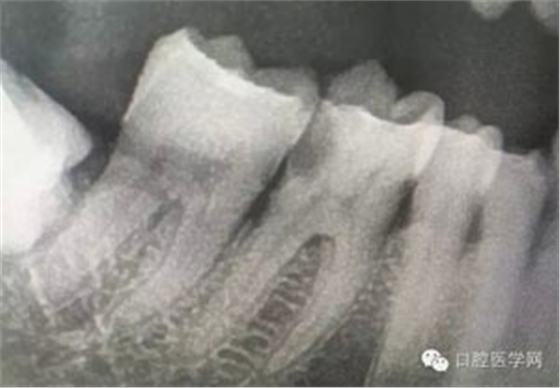

病例1:患者迫切希望保留自己的這一顆牙齒,根尖周陰影比較大,二度松動(dòng).而且旁邊有種植修復(fù)體,和患者溝通好后,治療好后觀察一個(gè)月后冠修復(fù),因?yàn)橛蟹N植的后期修復(fù),所以有了機(jī)會(huì)觀察,術(shù)后三個(gè)月和術(shù)后四個(gè)月,根尖恢復(fù)的還算不錯(cuò),希望能夠繼續(xù)觀察下去.這樣子的病例,做的時(shí)候我們一定要非常的小心,和患者要有充分的溝通以及不同科室的溝通然后決定怎么樣做比較好,假如就是出現(xiàn)了問題,到時(shí)候我們也比較好處理些,免得我們自己到時(shí)候不好收?qǐng)觥?/span> 病例2:364647中齲的樹脂充填,現(xiàn)在樹脂的充填材料非常之多,有些時(shí)候,我們感覺有了好的材料我們就可以做出好的修復(fù),可是這是在我們有扎實(shí)的基本功的基礎(chǔ)上的,我們可以沒有那么好的樹脂,那么多的顏色選擇,修復(fù)的那么的逼真,但是我們至少要恢復(fù)患者牙齒的功能,將腐質(zhì)去除干凈,薄壁弱尖消除掉,選擇好適應(yīng)癥,給患者以盡可能好的修復(fù)。 來源于KQ88